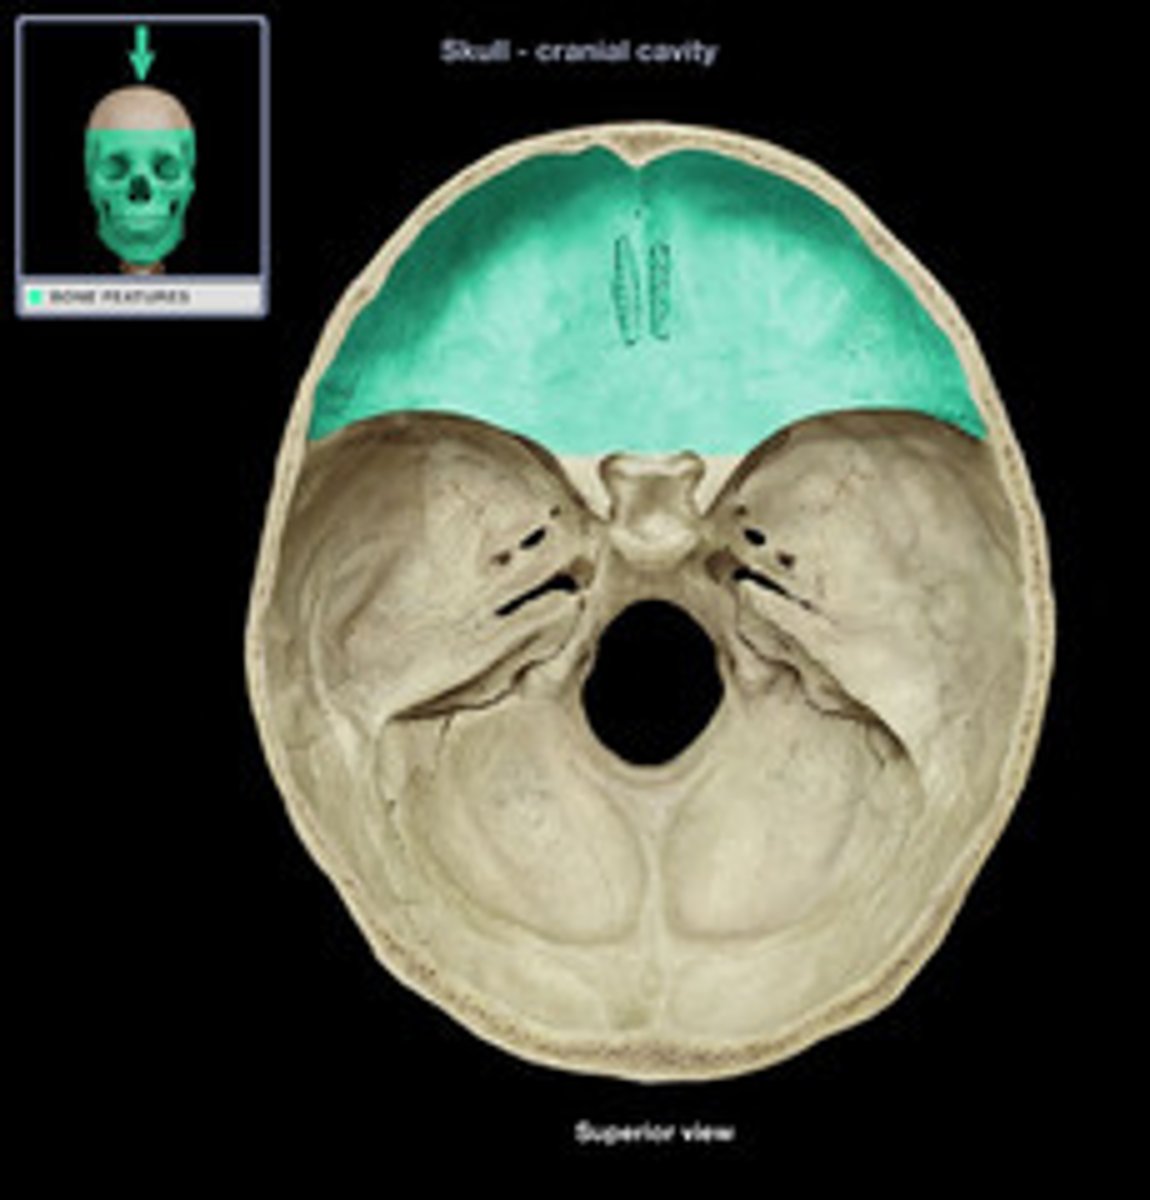

Crista galli

Vertical projection of the ethmoid bone.

Cribriform plate

Horizontal bone structure with olfactory foramina.

Body

Central part of the ethmoid bone.